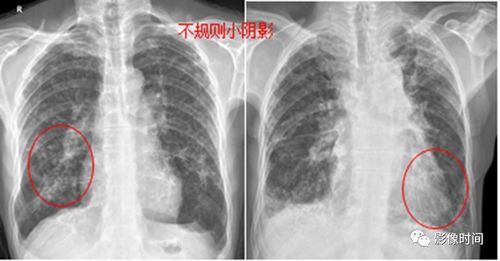

肺部有阴影,肺部有阴影是什么原因

又一个病例讨论-咳嗽,黄痰,肺部阴影

肺部出现阴影可能预示多种疾病

肺部有阴影是什么原因

肺部阴影诊断

肺部阴影图片

肺部阴影图片胸片

肺部阴影x光片